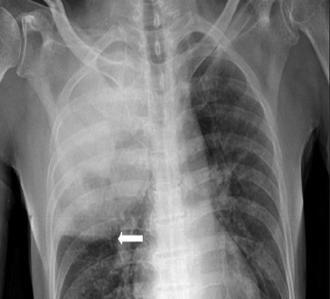

La obstrucción completa de la arteria provoca una elevación del segmento ST cóncava hacia abajo en derivaciones contiguas (> 1 mm en todas las derivaciones) . Por tanto, la localización del infarto se determina por las derivaciones, en las cuales se eleva el segmento ST:

Septal (obstrucción de ADA): V1-V2.

Anterior, incluido el ápex (obstrucción de ADA distal): V3-V4.

Lateral (obstrucción de arteria circunfleja): I, aVL (lateral alto) . V5-V6. (lateral bajo)

Anterior extenso (obstrucción de ADA proximal): V1-V6

Inferior o diafragmática (obstrucción de ADP, rama coronaria derecha): II, III aVF

3 (ENARM 2016) (ENARM 2010)

4 (ENARM 2017) (ENARM 2015) (ENARM 2011) (ENAM 2010) (ENAM 2010) (ENAM 2011) (ENAM 2017) (ENAM 2014) (ENAM 2019) (ENAM EXTRA 2020)